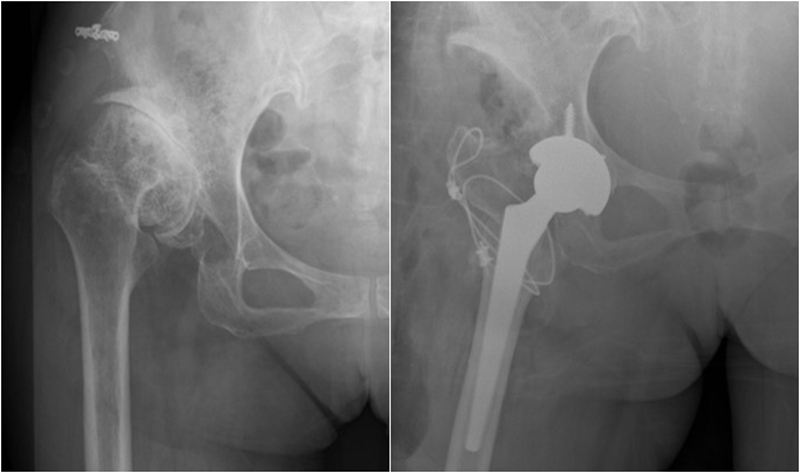

2、假体选择

①保留畸形:表面髋置换、短柄假体。

②让骨骼适应假体:股骨截骨。

③让假体适应畸形:组配式假体

④hybrid、水泥柄。

3、术中处理

①良好手术显露与软组织松解:充分的软组织松解、彻底清除紧张的瘢痕及关节囊;手术陈旧疤痕、切口设计。

②内固定的取出:良好术野,齐全工具。

③近端的重建:纠正性截骨,短缩截骨。

纠正性截骨的要求是:

①在畸形最严重的部位纠正对线不良;

②最大限度保留骨质;

③截骨部位牢固固定;

④使用长柄假体跨越截骨端。